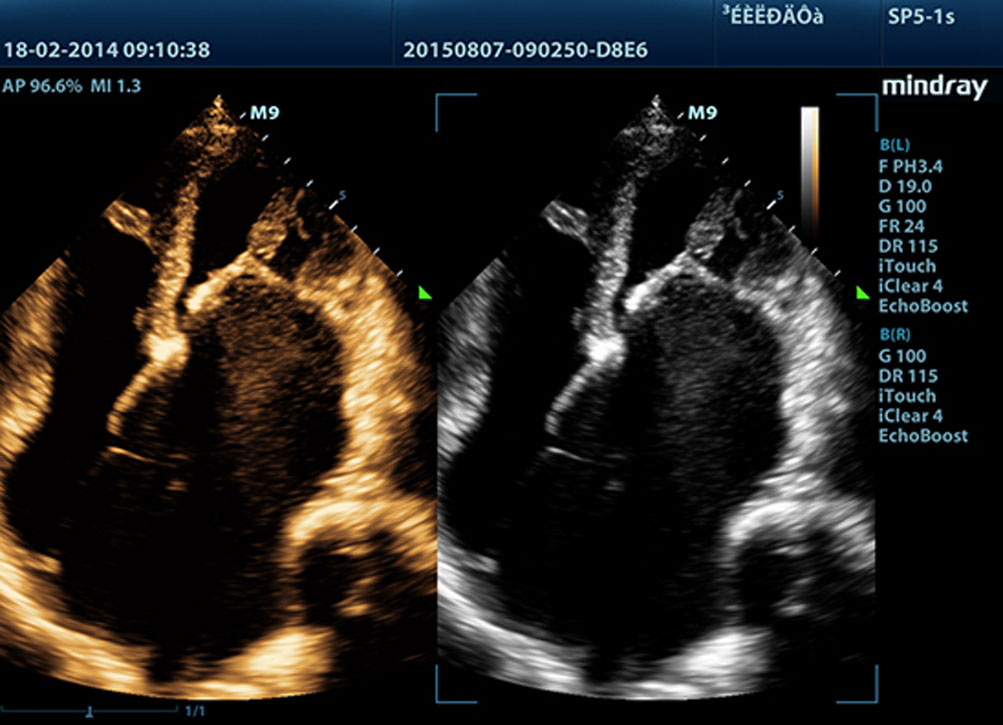

Echo Boost?

Teknologi pemrosesan sinyal adaptif Mindray yang unik dengan deteksi gema pintar, dirancang agar menggunakan informasi sinyal-ke-noise asli untuk menyempurnakan sinyal gema yang lemah sekaligus mengurangi suara bising di sekitar. Dengan demikian, dapat dihasilkan kecerahan gambar yang lebih seimbang dan visualisasi lapisan jaringan miokardium yang lebih baik.